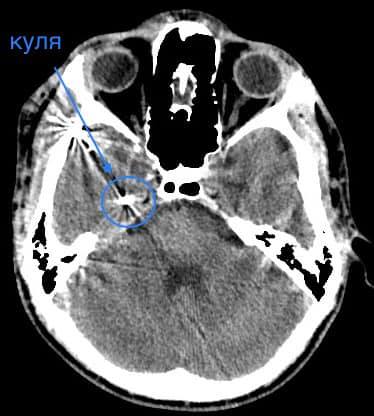

Як повідомив у Фейсбуці нейрохірург дитячої лікарні Михайло Ловга, у хлопця була куля в голові, що призвела до руйнації скроневої кістки та частини головного мозку.

«Ми виконали невідкладну операцію і вилучили стороннє тіло, видалили пошкоджені тканини і відновили цілісність збережених тканин. Добре, що куля зупинилась в 1 см від надзвичайно важливої судини і права скронева частка (яка пошкодилась в результаті травми) – функціонально незначима. Інакше, наш козак був би зовсім іншим, назавжди», – написав Михайло Ловга.